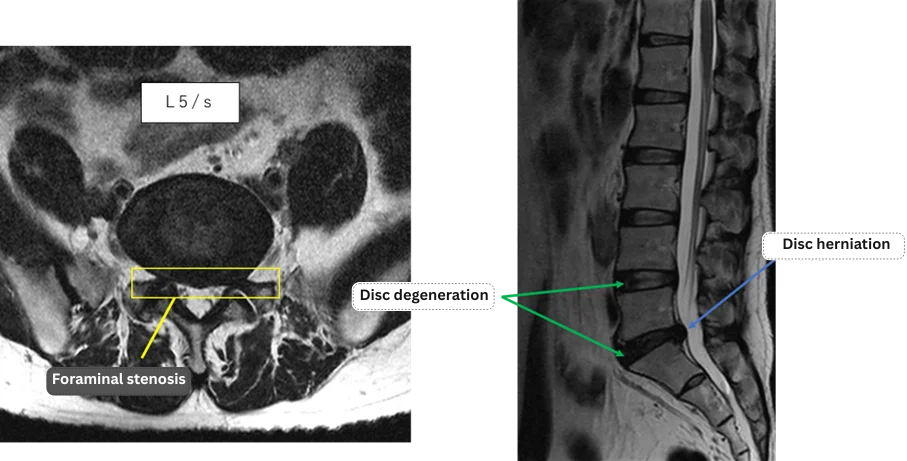

L1/2: Normal

L2/3: Normal

L3/4: Normal

L4/5: Disc degeneration

L5/S1: disc degeneration, disc herniation, foraminal stenosis

The above findings were also observed on the imaging.

The symptoms were attributed to disc degeneration, herniation and foraminal stenosis at the L4/5 and L5/S levels, which were likely compressing the nerve roots.